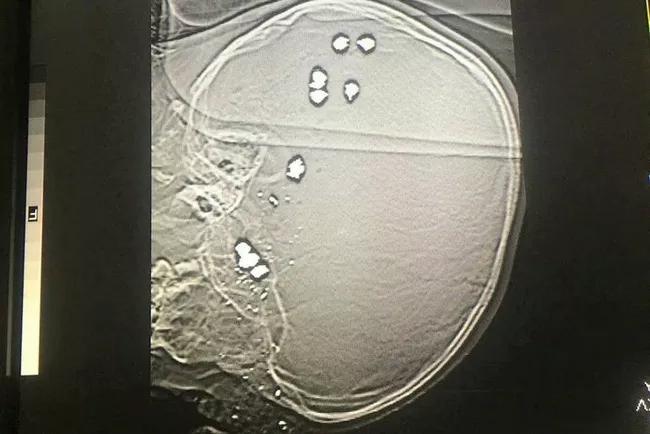

Tiến hành xét nghiệm, chụp chiếu, chúng tôi phát hiện trong đầu cháu có 11 viên đạn bi, không còn khả năng cứu chữa... Sau đó, gia đình cháu B.T.P đã xin làm thủ tục để đưa cháu về nhà và qua nguồn tin báo lại cho biết cháu P đã tử vong sau đó, thật xót xa".

Cháu B.T.P bị 11 viên đạn bi găm vào đầu. Ảnh: Bệnh viện Sản Nhi tỉnh Ninh Bình